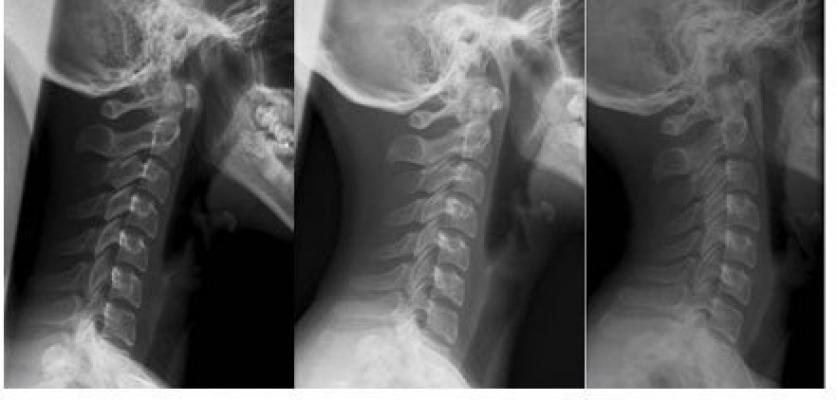

Boyunda fıtık ve düzleşme benzer semptomlar verir. Peki bizdeki şikayetin temelinde hangisi yatıyor? Klinikte sık ikileme düşüren bu yanılgının sebebi, düzleşmeye bağlı yalancı fıtık olabilmekte. Hem düzleşme hem fıtığınız varsa esas problemi bulmakta geç kalmayın.